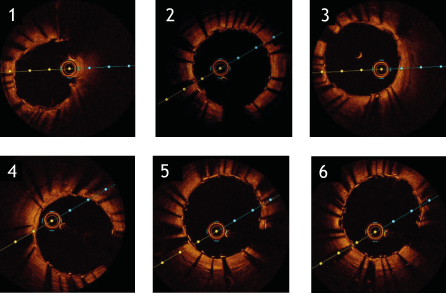

Figure 4. Optical coherence tomography of left artery descending from distal (1) to proximal (6) after implantation of Magmaris-BVS (22.04.2020). The „malapposition“ of the Magmaris- BVS in (2), (3) and (4) was taken into account without further intervention due to the anticipated resorption of the struts.

In our patient suffering from angina CCS 3 arising from 2 vessel disease, a strategy of staged PCI was pursued. We started with the PCI of the RCA which was successfully completed with the implantation of 3 DES. Although intracoronary imaging of the acute result of this PCI was not performed, angiography indicated proper stent sizing and no signs of procedural complications. 3 months later, PCI of the LAD was scheduled which a priori was a complex situation because the target stenosis was in direct neighborhood with a dilated vessel segment so that the risk of acute stent malapposition had to be considered. Therefore, after individual risk- benefit evaluation the decision was made to use a bioresorbable Magmaris-BVS to treat this lesion. The decision was based on the assumption that the stenosis would be sufficiently covered by the BVS whereas in segments where the scaffold would not reach the ectatic vessel wall an accelerated resorption of the “malapposed” struts would take place. The magnesium-based Magmaris-BVS was preferred over other BVS as it had been shown previously that PLLA-based scaffolds are linked to unfavorable longterm outcomes [5] which has not been described for Magmaris [6,7]. 11 months later, follow-up examination indeed showed an excellent morphological result in the LAD without restenosis and complete resorption of the scaffold as intended. However, OCT analysis of the previously implanted